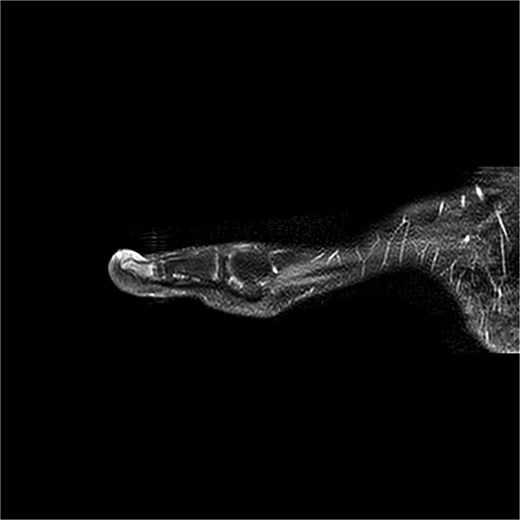

A 12-year-old male presented with pain and deformity of the right great toe (Fig. 1). MRI confirmed SE with osteomyelitis (Fig. 3). Bone cultures grew S. aureus and Staphylococcus lugdunensis with moderate growth in one of five samples. After 1 week of intravenous therapy, treatment was completed with oral dicloxacillin. At 17- and 39-day follow-up visits, the patient was pain-free with no signs of infection (Fig. 2).

Case 2

Case 3

SE, although benign, can cause significant pain and deformity if not promptly diagnosed and treated, both regarding the exostosis and osteomyelitis. Our cases demonstrate that osteomyelitis may develop as a direct consequence of the chronic irritation, bone exposure, microtrauma, or low-grade infection associated with SE. Radiographic imaging is pivotal in diagnosing osteomyelitis in otherwise clinical SE lesions, with MRI being the golden standard. Intraoperative bone cultures provide essential confirmation of osteomyelitis and identify the bacterial species involved, along with their antibiotic sensitivity.